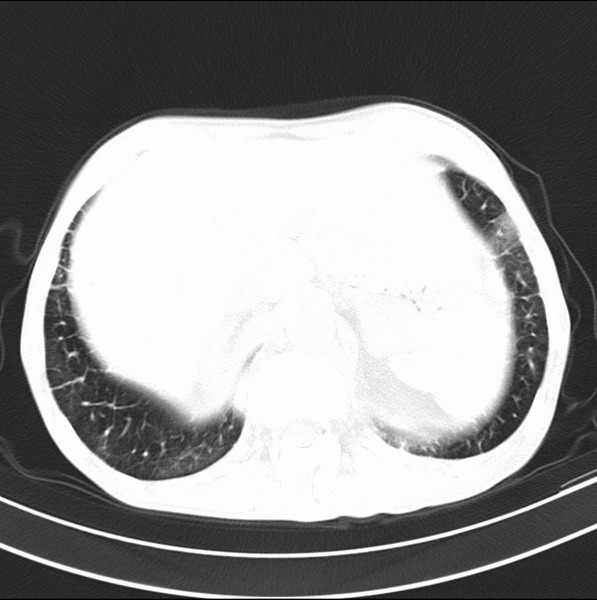

标题: CT19600:能否诊断为转移?

女、55

3年前盲肠癌、一年半前诊断膀胱癌,现在呼吸困难,临床考虑为肺转移

请问胸部ct如何诊断?能否排除淋巴管炎,纵隔窗没有问题。

考虑间质性病变,癌性淋巴管炎可能.

转移,癌性淋巴管炎。

建议抗炎后复查,不除外癌性淋巴管炎。

炎性并间质纤维化,请询问病史,如用过平阳霉素或其他化疗药.可能为药物引起的间质纤维化.